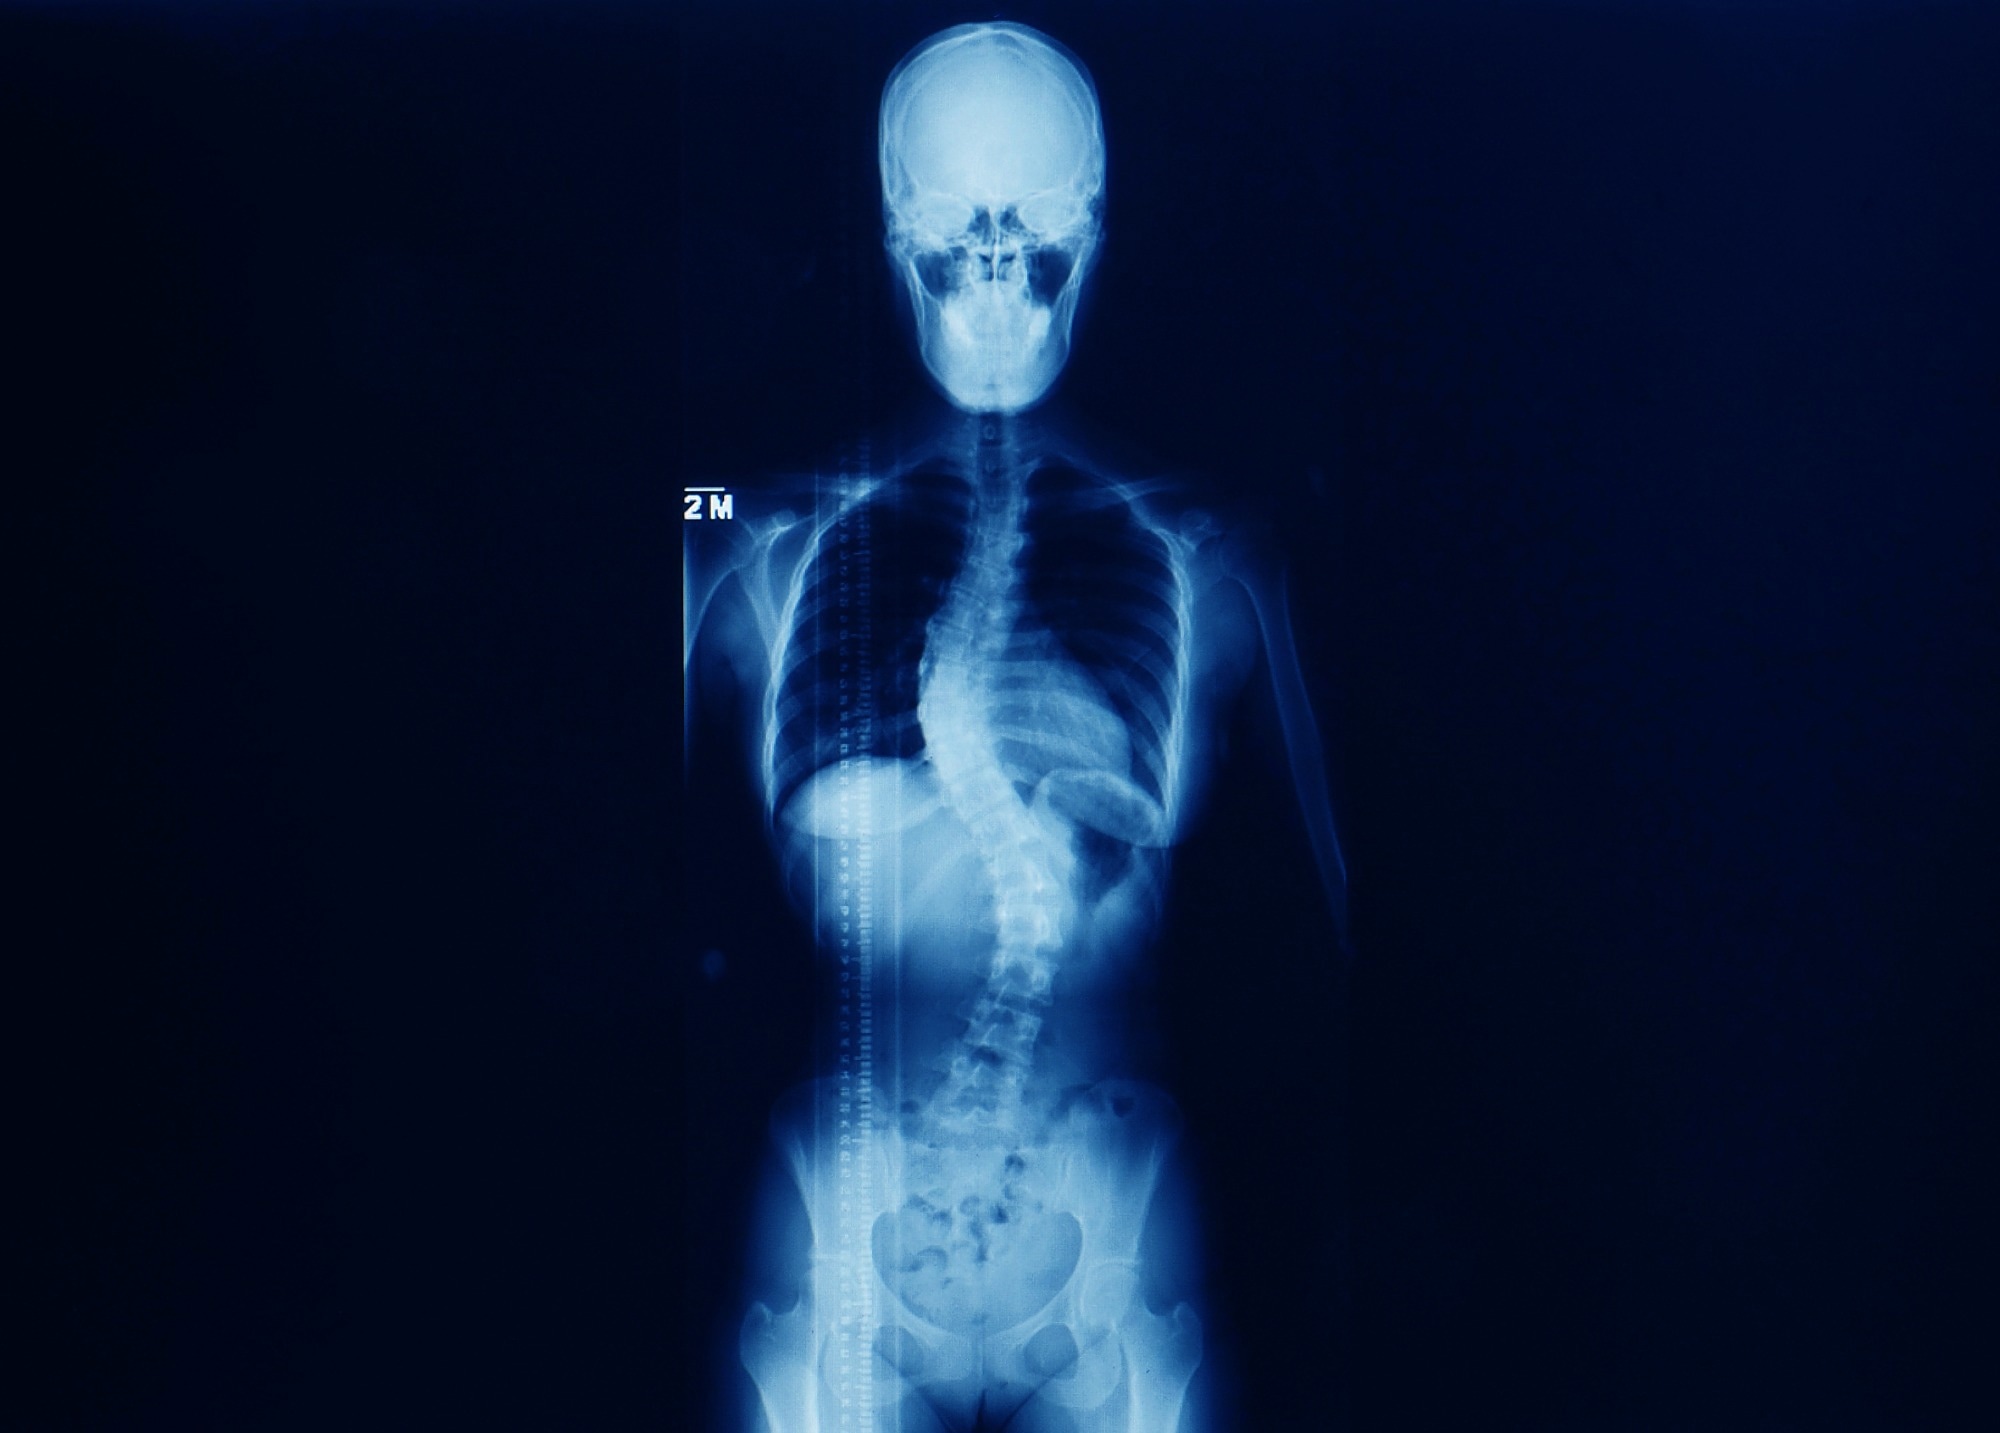

Study: Deep Learning Model to Classify and Monitor Idiopathic Scoliosis in Adolescents Using a Single Smartphone Photograph. Image Credit: Yok_onepiece/Shutterstock.comStudy: Deep Learning Model to Classify and Monitor Idiopathic Scoliosis in Adolescents Using a Single Smartphone Photograph. Image Credit: Yok_onepiece/Shutterstock.com

AIS is a three-dimensional (3D) spinal malformation that affects boys and girls in early adulthood, often hindering quality of life (QoL). AIS reduces mobility by triggering back pain and induces cardiopulmonary impairment, which makes its early diagnosis crucial.

AIS diagnosis requires physical examinations, including shoulder height, thoracic cavity asymmetry, rib and breast deformity, and waist asymmetry.

Even when done by experienced clinicians, AIS diagnosis based on the external appearance does not reliably detect the specific malformation severity and type, raising the need for radiographic examinations.

However, repeated radiographic examinations increase patient's radioexposure and potential health risks. Yet, it is necessary to guide AIS management, e.g., bracing correction for moderate spine malformation and spine surgery in cases of severe malformation.